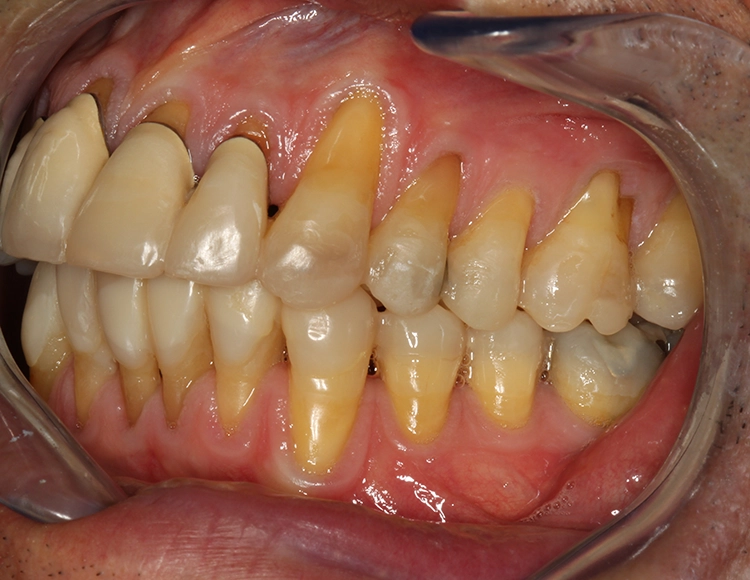

Egger/Wermuth/GrevenRote Ästhetik: Im Ober- und Unterkiefer zeigten sich generalisiert ausgedehnte Rezessionen mit bis zu 8 mm Attachmentverlust vor allem im Bereich der Eckzähne (Miller-Klasse III; Rezessionstyp [RT] 2 [69]. Das Band an keratinisierter Schleimhaut ist durchgehend vorhanden. Die Breite variiert im Eckzahnbereich von 1 mm bis zu 2 mm im Bereich der Unterkieferfrontzähne, der Prämolaren und Molaren (Abb. 1). Die fazialen Rezessionen sind mit approximalem röntgenologischem Attachmentverlust im koronalen Wurzeldrittel (Abb. 2) und Papillenverlust im Bereich zwischen den Kontaktpunkten und der approximalen Schmelz-Zement-Grenze assoziiert (Abb. 1). Der Patient verfügt über eine schmal geformte Oberlippe. Die Lachlinie verläuft mittelhoch (Abb. 3).

Dentalstatus: Es zeigen sich generelle Abrasionen, Attritionen und Erosionen im Ober- und Unterkiefer. Die ursprüngliche anatomische Kauflächenstruktur in den Seitenzahnbereichen ist durch die massiven erosions- und attritionsbedingten Zahnhartsubstanzverluste nicht mehr vorhanden (Tab. 2). Aufgrund der massiven Zahnschmelzverluste erscheint die Zahnfarbe insgesamt gelblicher. Der Patient wünscht sich im Rahmen der Rehabilitation in dieser Frage eine merkliche Verbesserung.

Egger/Wermuth/GrevenAbb. 8 und 9: Rechts-links-Okklusion.